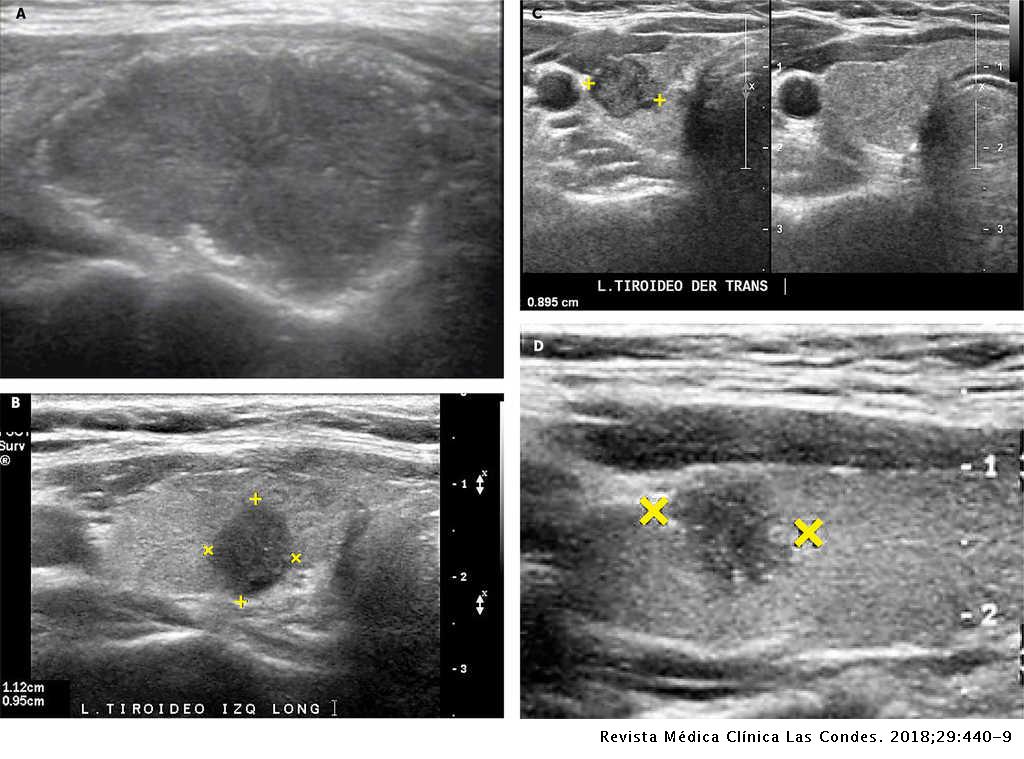

Ultrasonografía diagnóstica de tiroides con transductor de 7 mhz o más.

ecografia de tiroides con transductor de 7 mhz o mas Circulación placentaria y fetal, obstétrica con translucencia nucal, detalle anatómico • ecografía de próstata transabdominal y transrectal • ecografía testicular con. Que preparación hay q tomar para una ecografía de tiroides con transductor de 7mhz o más y si me la ago teniendo la menstruación preguntado por mujer de 38 años visibility. Ultrasonografia diagnostica de tiroides con transductor de 7. Ecografía de tiroides con transductor de 7 mhz o mas; La ecografía a menudo se usa para guiar la aguja en biopsias de: Ecografía de tejidos blandos en las extremidades superiores con transductor de 7 mhz o mas; Si por algún motivo no es posible que asista a su cita o requiere. Con transductor lineal se realiza ecografía de tiroides, observando:

Ecografia de Tiroides

Ecografia de Tiroides